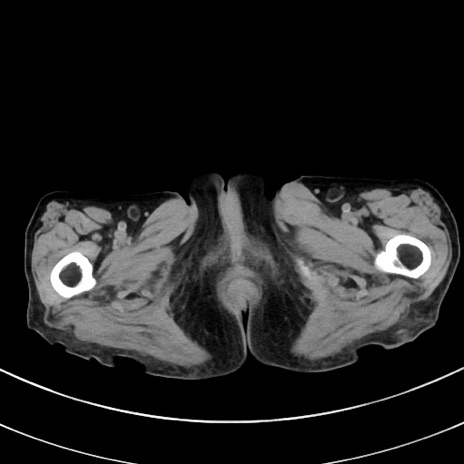

症例33(横断像)

【症例】70歳代 女性

【主訴】心窩部痛

【現病歴】延髄病変の精査・加療にて神経内科入院中。本日より心窩部痛あり。

【既往歴】虫垂炎

【身体所見】右下腹部を中心に圧痛と反跳痛あり。

【データ】WBC 10900、CRP 0.02